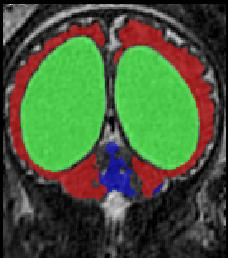

Limiting failures of machine learning systems is of paramount importance for safety-critical applications. In order to improve the robustness of machine learning systems, Distributionally Robust Optimization (DRO) has been proposed as a generalization of Empirical Risk Minimization (ERM). However, its use in deep learning has been severely restricted due to the relative inefficiency of the optimizers available for DRO in comparison to the wide-spread variants of Stochastic Gradient Descent (SGD) optimizers for ERM. We propose SGD with hardness weighted sampling, a principled and efficient optimization method for DRO in machine learning that is particularly suited in the context of deep learning. Similar to a hard example mining strategy in practice, the proposed algorithm is straightforward to implement and computationally as efficient as SGD-based optimizers used for deep learning, requiring minimal overhead computation. In contrast to typical ad hoc hard mining approaches, we prove the convergence of our DRO algorithm for over-parameterized deep learning networks with ReLU activation and a finite number of layers and parameters. Our experiments on fetal brain 3D MRI segmentation and brain tumor segmentation in MRI demonstrate the feasibility and the usefulness of our approach. Using our hardness weighted sampling for training a state-of-the-art deep learning pipeline leads to improved robustness to anatomical variabilities in automatic fetal brain 3D MRI segmentation using deep learning and to improved robustness to the image protocol variations in brain tumor segmentation. Our code is available at https://github.com/LucasFidon/HardnessWeightedSampler.